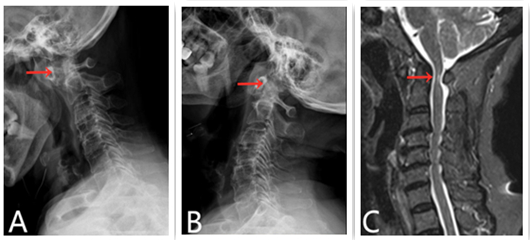

郭阿姨今年 75岁,1年前开始出现四肢麻木的症状,一直忍到近1个月她开始出现经常掉筷子、行走不稳、手脚无力等症状,才到医院进行检查。经骨伤三科专家诊查,颈椎X线提示寰枢椎关节在低头时处于明显脱位状态(下图A箭头所示),仰头时复位(下图B 箭头所示),提示寰枢椎明显不稳,而MRI显示脊髓已经受压变性(下图C 箭头所示),急需进行手术治疗。